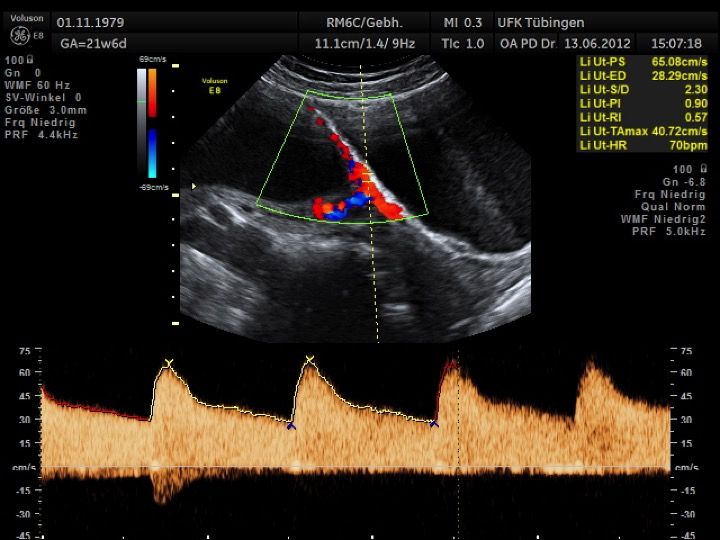

Mithilfe des Ersttrimester-Screenings kann das persönliche Risiko einer Präeklampsie bestimmt werden. Dazu wird die Vorgeschichte der Schwangeren, der aktuelle Blutdruck, das Ergebnis der Ultraschalluntersuchung (Widerstand in den Gebärmutter-nahen Gefäßen) und der Blutabnahme bei Ihnen (PAPP-A) kombiniert. Sollte das Risiko über 1:100 sein, empfehlen wir die tägliche Einnahme von Aspirin 150mg bis zu 35.SSW und eine gezielte Überwachung der weiteren Schwangerschaft.